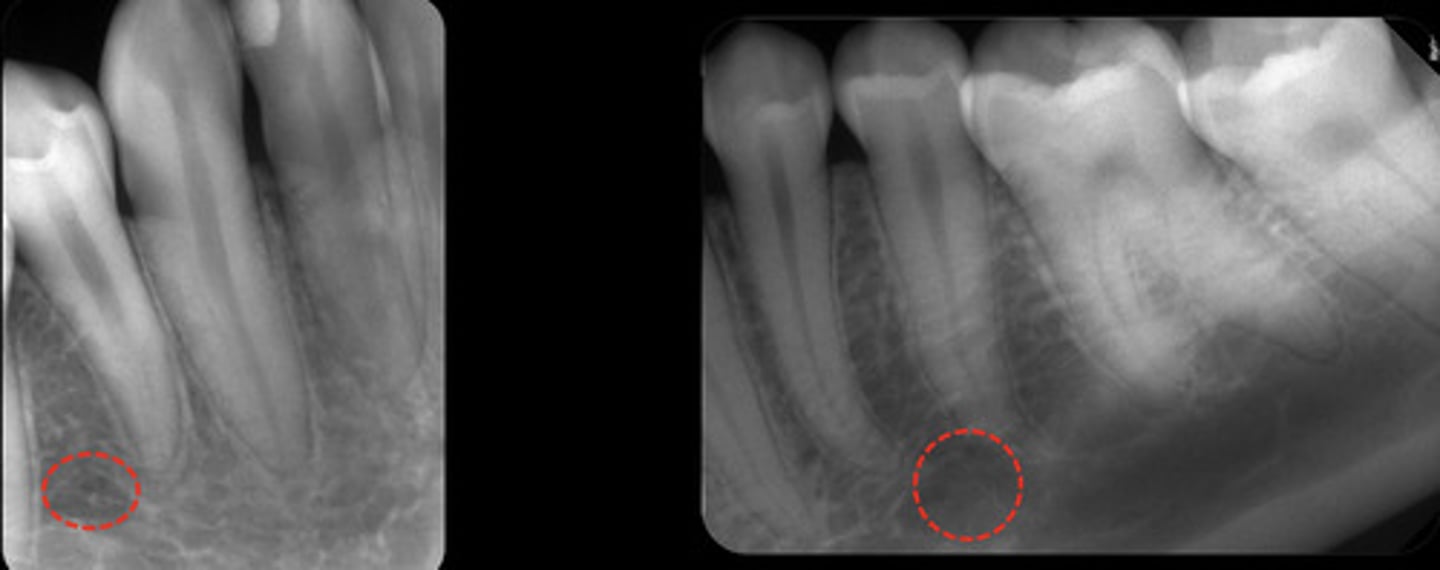

What is the mandibular canal?

What does the mandibular canal look like radiographically?

information on mandibular canal

radioluncentt band, with two thin radiopaque line & below the apices of the mandibular molar teeth